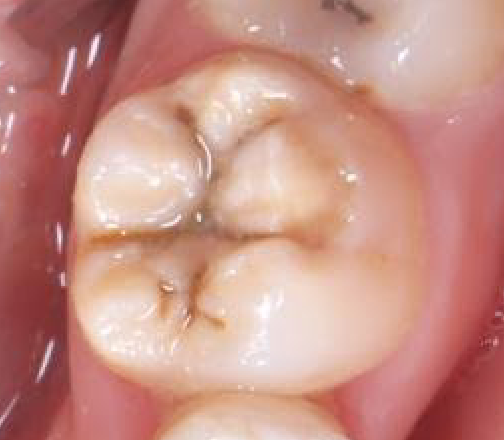

➡️溝が虫歯になってしまった奥歯